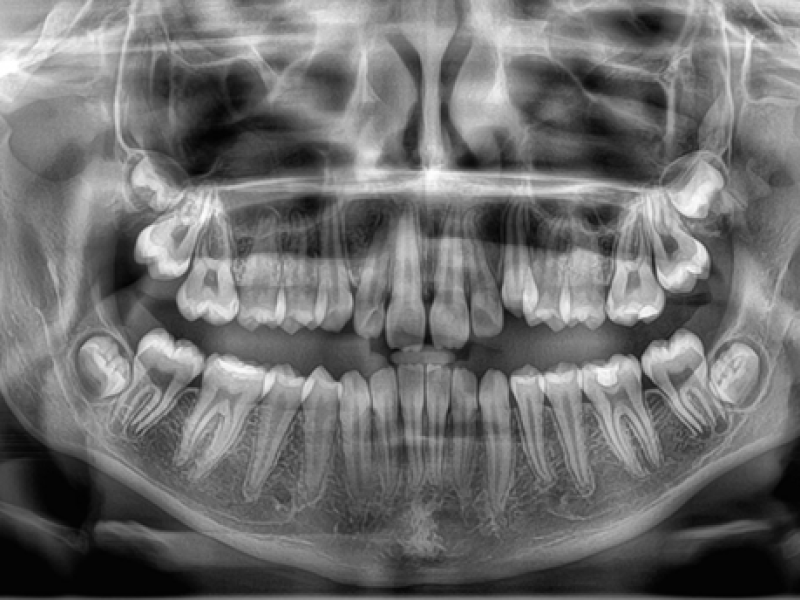

En el centro de Radiologia Maxilo Facial Dr. Mayor nos hemos mantenido a la vanguardia en el sector y por eso somos uno de los centros de referencia a nivel nacional en la realización de estudios maxilofaciales. Además, podemos decir que somos uno de los primeros centros que incorporó la tecnología 3D a sus instalaciones, lo que nos permite hacer estudios muy avanzados y completos, como los TAC dentales (Dentascan, Cone Beam CT) dirigidos a todo tipo de pacientes.

En los centros de Imagen Diagnóstica Dental Dr. Mayor ofrecemos una amplia variedad de servicios, gracias a la moderna aparatología con las que contamos.

Las pruebas diagnósticas que realizamos en nuestro centro son las siguientes: